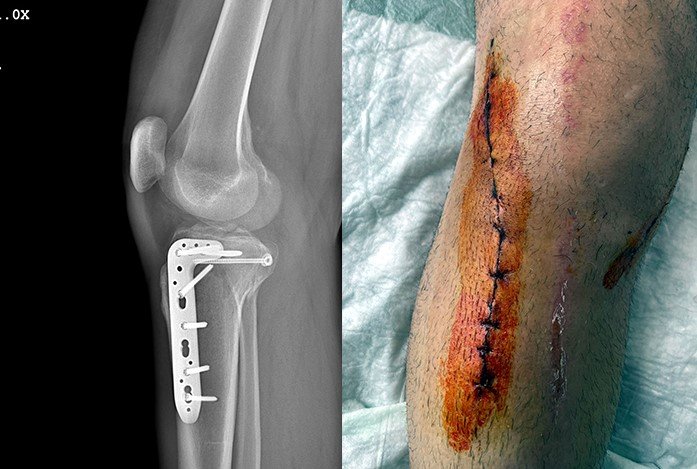

- Araçtan indikten sonra kendisine "Ne yapıyorsun, aklın başında mı?" diye sordum. Cevap vermeden bana doğrudan yumruk attı. Sonra omuzlarıma baskı uygulayarak saldırı tekniğiyle ayaklarımın üzerine basıp bir bacağımı iki yerinden kırdı.

Olayın ardından büyük kızımdan öğrendim, o esnada şahsın beline silah taktığını söyledi. Onlar olay yerinden uzaklaştıktan sonra eşimin yardımıyla arabama bindim. Aracın içinde emniyete olayı bildirdim. Sonra kısa bir süre içinde hastaneye gittik ve kırık bacağım için hemen ameliyat oldum. Ailemle birlikte aniden dehşet yaşadık. Olay günü eşim ve çocuklarım yanımdaydı.